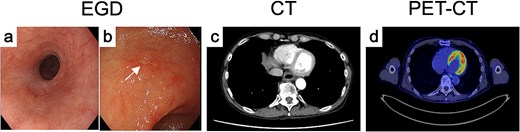

The final diagnosis was advanced, unresectable ESCC of the middle thoracic esophagus (Mt, SCC, cT3brN1M1b [IM-St], stage IVb). The patient received three cycles of CF plus pembrolizumab. Post-treatment evaluation showed fibrotic scarring at both sites (Fig. 3a and (b)), and biopsies revealed no residual tumor. CT and PET-CT demonstrated marked regression and no abnormal FDG uptake (Fig. 3c and d). The overall response was judged as a partial response, and conversion surgery was planned.

Endoscopic, CT, and FDG-PET findings after treatment. After induction chemoimmunotherapy, both (a) the primary tumor and the (b) IM markedly shrank. (c) CT and (d) FDG-PET findings of primary tumor after treatment.